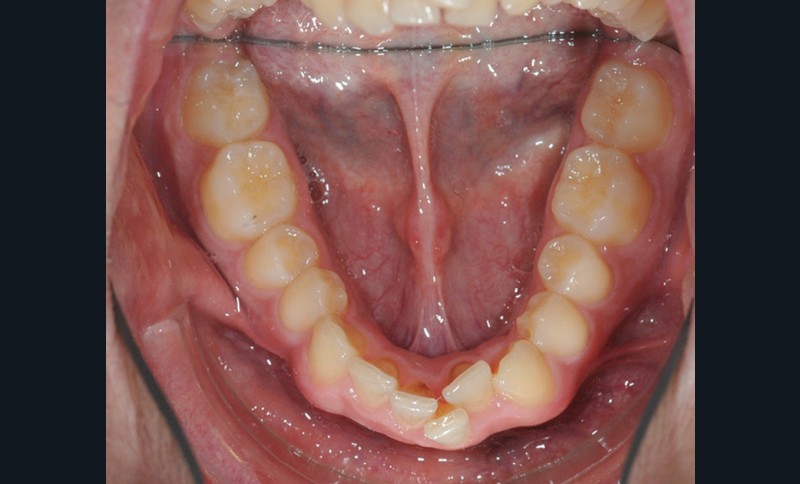

C’est à ces questions que nous permettront de répondre les deux premiers conférenciers, parodontologistes : le Dr Béatrice Straub nous présentera le renfort parodontal minéralisé, technique qu’elle a développée et pratique depuis de nombreuses années, pour éviter les préjudices des mouvements orthodontiques à risque, notamment lors des décompensations préchirurgicales (fig. 1a-d) ; le Pr Anton Sculean abordera le thème des greffes, avec leurs indications, les différentes techniques à privilégier et illustrera ses propos par de nombreux cas cliniques aux résultats esthétiques impressionnants.

La matinée s’achèvera par le traitement de la dysharmonie dent-arcade par des techniques chirurgicales originales et novatrices : l’expansion transversale maxillo-mandibulaire (Dr Jean-Luc Ouhioun, fig. 2a-h) et la distraction sagittale du bloc incisivo-canin « front-block de Triaca » (Dr Olivier Esnault).